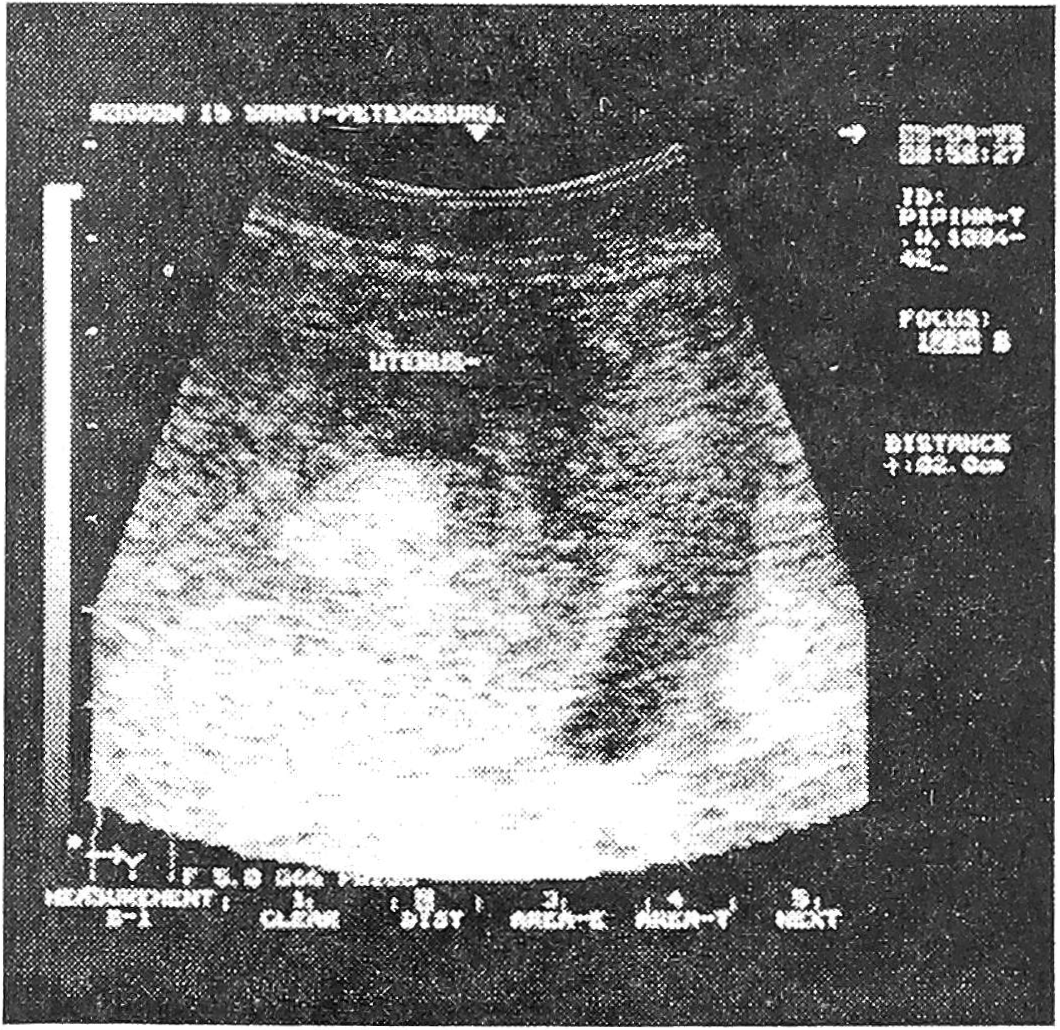

2. Субинволюция матки (рис. 1).

Рис.1. Субинволюция матки.

В данном случае при ультразвуковом исследовании определяется расширенная полость, содержащая небольшое количество сгу-

стков и/или жидкой крови, или остатки оболочек и плацентарной ткани. При этом клинически значительно затягивается период кровянистых выделений, температурная реакция в первую неделю чаще отсутствует - матка по величине может быть нормальной, но тонус ее снижен ( то есть при пальпации она представляется мягковатой).